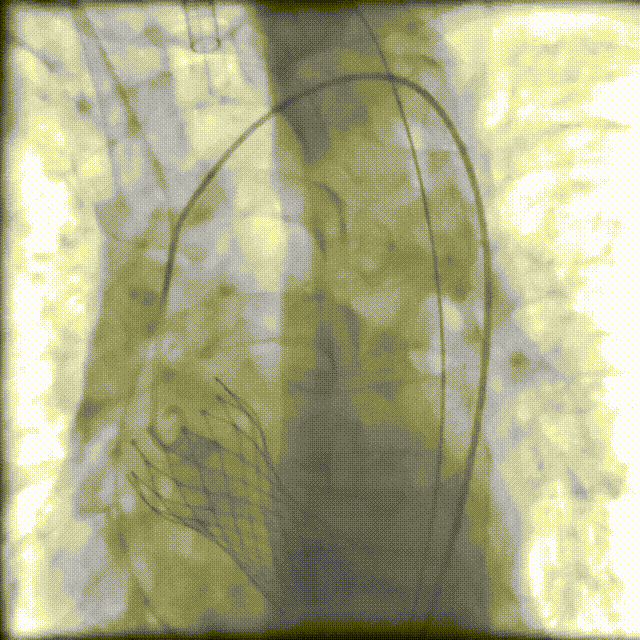

术后造影

术中,我院心血管内科、手术麻醉科、介入医学科、超声医学科、ICU、呼吸与危重症医学科、胸心血管外科、输血科等医护专家组成“护心团队”,在四川大学华西医院心血管内科魏家富教授团队的指导和护航下,经股动脉入路建立工作路径,成功置入新的人工主动脉瓣(VenusA-Plus瓣膜)。术后造影及超声提示未见明显反流,无瓣周漏,瓣膜置入位置良好,形态完整,术后跨瓣压差及舒张压即刻改善,未出现相关并发症,手术圆满成功。目前,患者已顺利出院!